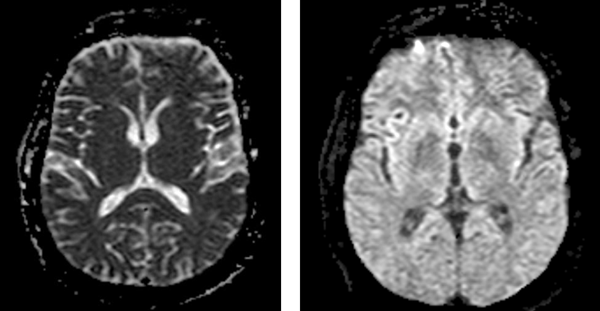

Figure 2. MRI brain without and with contrast showing enhancement of meninges